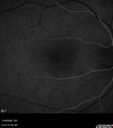

Acute Retinal Pigment Epitheliitis (Krills disease)2 views15 year old with sudden central vision loss in one eye. The vision loss persisted though for at least 6 months (which may be a laser injury)Apr 13, 2026